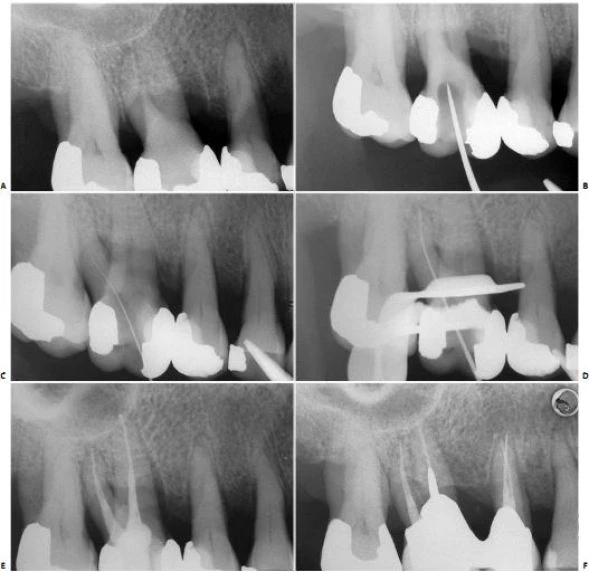

Ở những ống tủy cong, vị trí thành xoang đối diện với đoạn cong chân răng phải được mở rộng (hình 11.14). Nhằm đảm bảo dụng cụ không bị cong hơn so với độ cong vốn có của chân răng. Tương tự như lúc xe chạy vào khúc cua vậy, người ta thường tăng bán kính khúc cua để xe không bị chạy ra khỏi làn đường.

Hình 11.14. A. Phim trước điều trị R36: chân gần cong 1/3 trên. B. Mở đầu bằng trâm số #8 đi vào ống ngoài gần, nhận thấy ống tủy cong về phía xa và phía lưỡi. C. Xoang tủy được mở rộng về phía gần và phía má, phạm vào múi gần ngoài. D. Trâm số #20 có một đường vào thẳng đến 1/3 chóp của ống tủy.

Hình 3.15. A. Phim răng cối lớn 1 hàm trên, chân răng gần ngoài bị cắt vì lý do nha chu. B. Mở lối vào ống tủy, tháo đê cao su để clamp không gây trở ngại cho việc chụp phim kiểm tra lỗ vào ống tủy. C. Dùng file 06 ở chân xa ngoài sau khi chân trong đã được tìm thấy, làm sạch và tạo hình. Nên tháo đê cao su để tiện cho việc kiểm tra ống tủy. Cán dụng cụ nên buộc vào chỉ nha khoa và buộc đầu chỉ còn lại bên ngoài. D. Đặt lại đê cao su và hoàn thành việc điều trị theo cách truyền thống. E. Phim sau điều trị. F. Sau 4 năm.